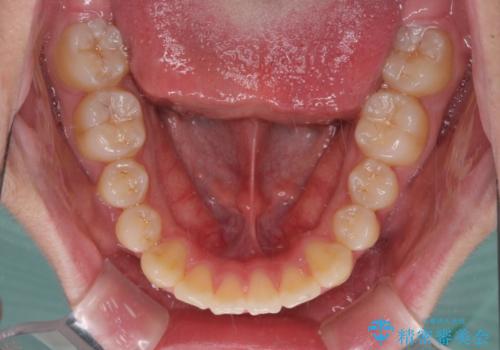

- 矯正装置

- 審美装置

- 上下前歯のデコボコを改善したいとのことで来院された患者様です。

中学生と言うこともあり、1年強の短期間で終了しました。

歯磨きがしっかりとできないと虫歯になるリスクがありましたが、治療期間中は清潔な状態を保っていただけました。